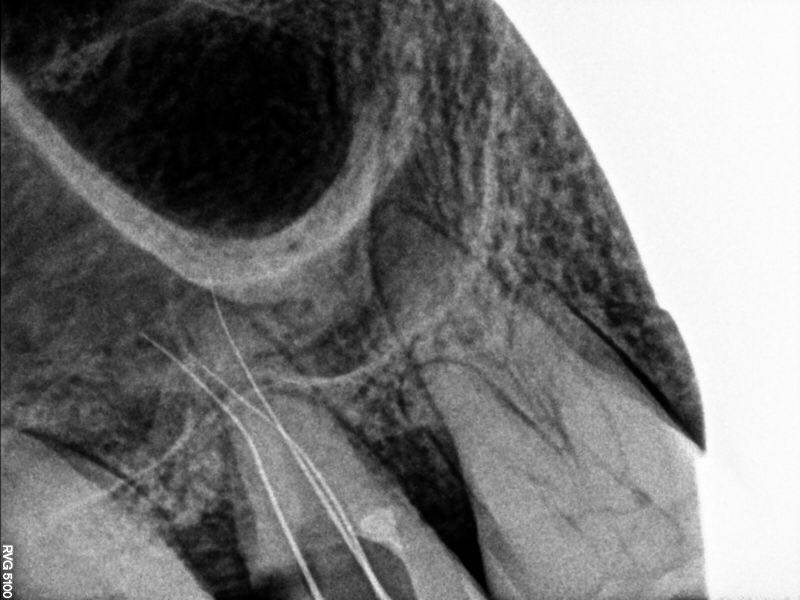

行近中壁侧穿修补,之后在显微镜下ET20暴露根管口,三根,均行疏通,扩锉根充

此病例,最大的难点就是髓石堵住根管口,导致根管异常难以进入,显微镜在复杂根管治疗这方面确实非常优秀。另外这个病例会侧穿主要还是太大意了,以为用了超声就万事大吉,慎之慎之